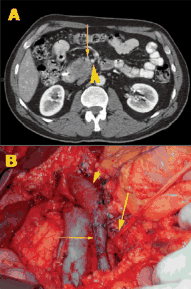

This slide show features a CT image, and pathology images of gastrointestinal stromal tumors (GISTs) arising in the stomach using H&E, CD34, and c-Kit staining.